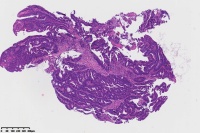

中分化腺癌?

性别

女

年龄

67岁

临床诊断

一般病史

直肠占位

标本名称

大体所见

腺癌(低一中 分化)

中分化腺癌